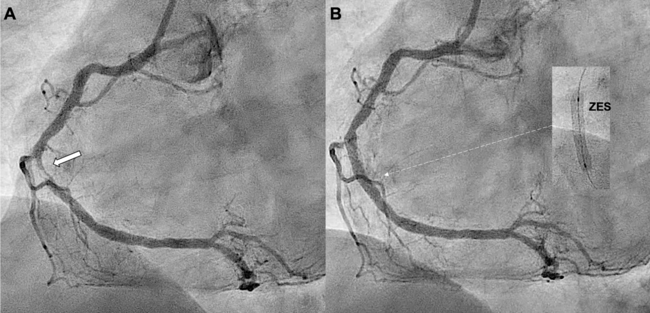

Video 1. Index coronary angiography showing a critical lesion in the middle right coronary artery and the final result after implantation of the zotarolimus-eluting stent, without immediate complications.